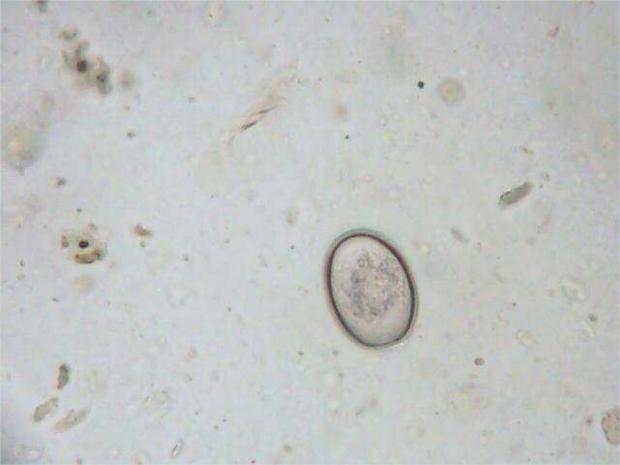

Ascaridia Columbae

Bem conhecida pela maioria dos columbófilos como lombriga ou bicha, este parasita (nemátode) é visto ocasionalmente nos excrementos do seguimento da rotina de desparasitação.

Ciclo de Vida

O ciclo de vida é directo. O verme adulto põe ovos numerosos que são passados pelas fezes e dependendo do calor e humidade, passam por um processo de maturação de pelo menos duas semanas.

Depois do processo de maturação estar completo os ovos tornam-se um foco de infecção e se forem ingeridos através de comida ou água contaminada vão libertar as suas larvas dentro do intestino.

As larvas penetram o epitélio de revestimento intestinal e permanecem na parede intestinal aproximadamente 10 a 14 dias, depois disso retomam ao lúmen do intestino. Os ovos aparecem nas fezes dos pombos 37 a 42 dias após a infecção.

Eimeria é o tipo de protozoários que causam a doença, Coccidiose.

Ovo de Coccidiose